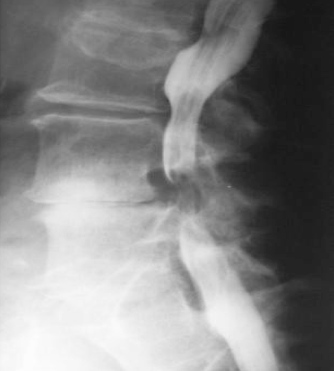

Chirurgie orthopédique et traumatologique

Interventions chirurgicales

Colonne vertébrale